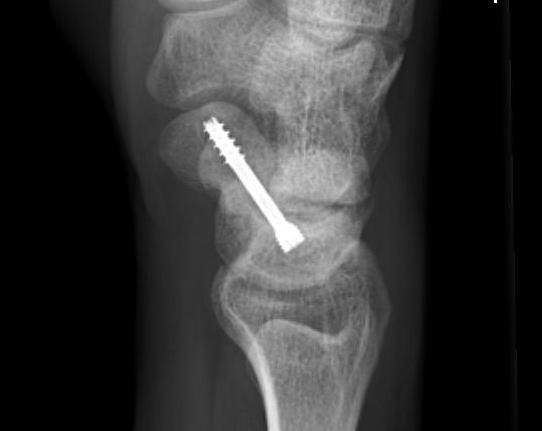

Scaphoid waist fracture 1 mm displaced

Scaphoid fracture with significant displacement

Scaphoid proximal pole fracture